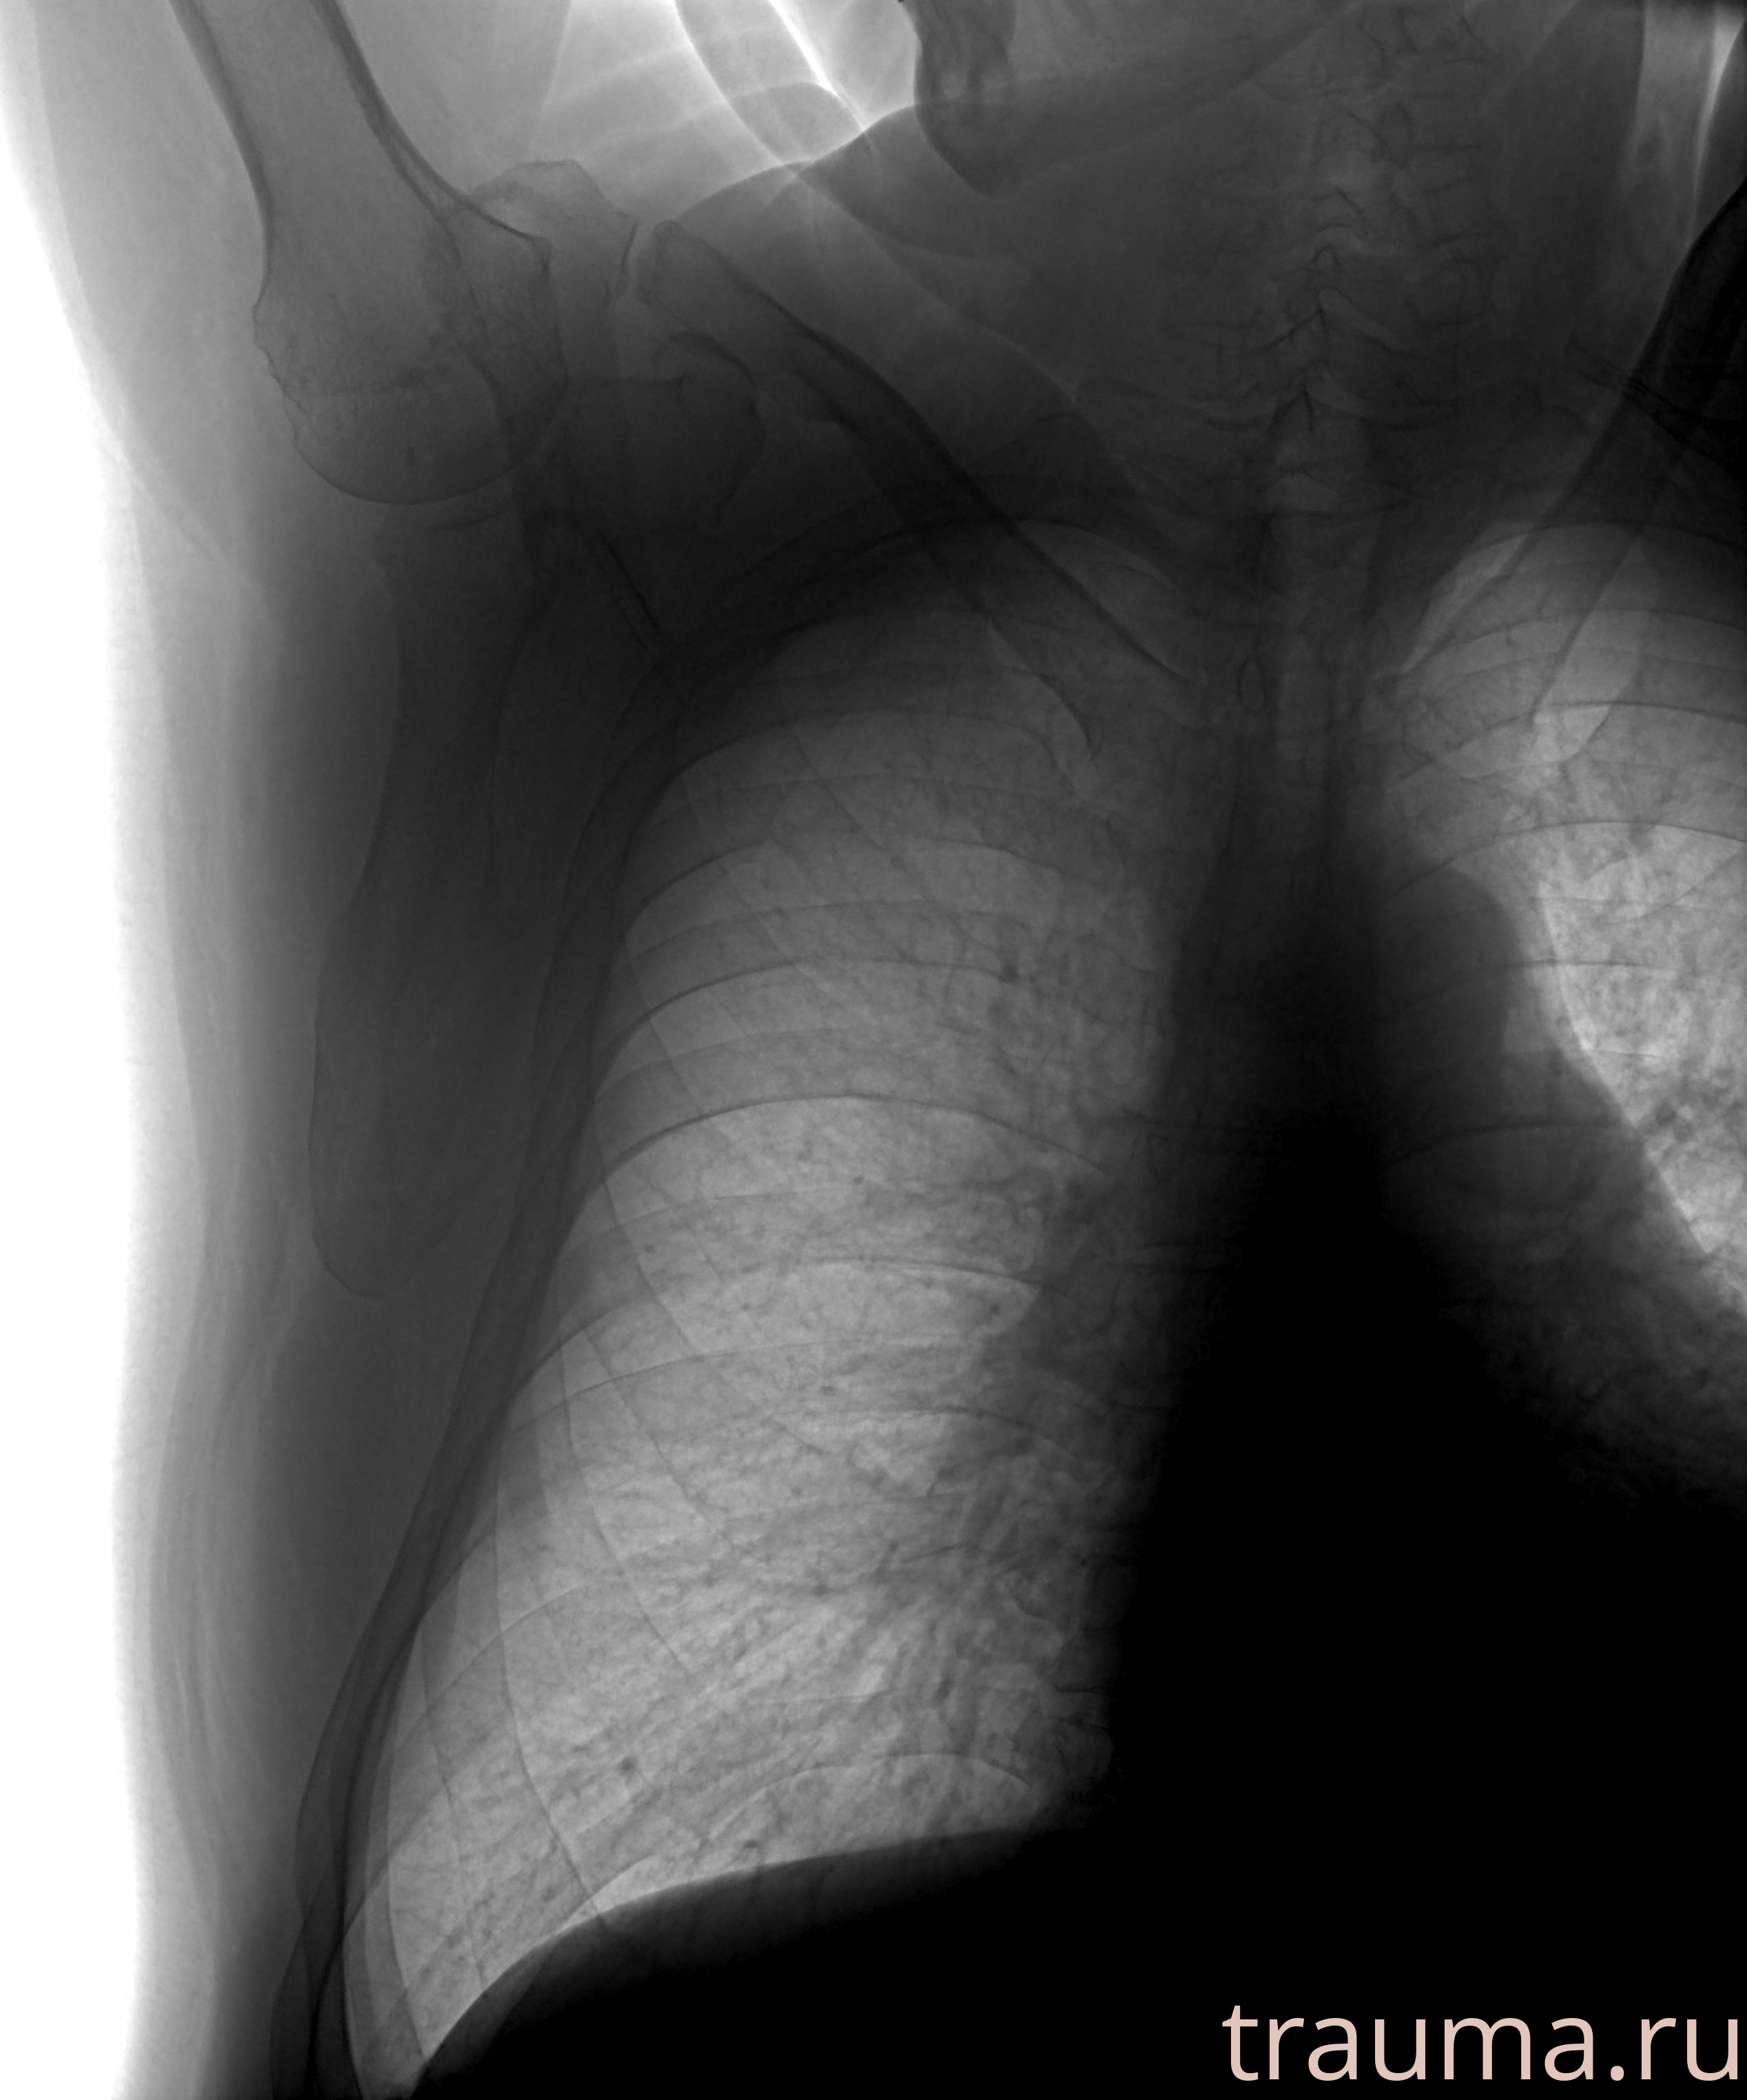

Рентгенограммы

Рентген на дому: по вашему адресу приезжает врач-рентгенолог, травматолог-ортопед с мобильным рентгеновским аппаратом, проводит диагностику травмы или заболевания, делает необходимые рентгенограммы, дает рекомендации по дальнейшему лечению. Получить качественные снимки в домашних условиях возможно благодаря уникальной методике, разработанной МосРентген Центром для института  Склифосовского

при переломе шейки бедра и пневмонии от компании МосРентген Центр - партнера Института имени Склифосовского